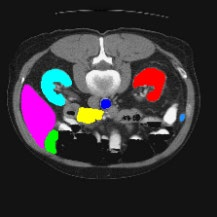

Transformers have made remarkable progress towards modeling long-range dependencies within the medical image analysis domain. However, current transformer-based models suffer from several disadvantages: (1) existing methods fail to capture the important features of the images due to the naive tokenization scheme; (2) the models suffer from information loss because they only consider single-scale feature representations; and (3) the segmentation label maps generated by the models are not accurate enough without considering rich semantic contexts and anatomical textures. In this work, we present CASTformer, a novel type of generative adversarial transformers, for 2D medical image segmentation. First, we take advantage of the pyramid structure to construct multi-scale representations and handle multi-scale variations. We then design a novel class-aware transformer module to better learn the discriminative regions of objects with semantic structures. Lastly, we utilize an adversarial training strategy that boosts segmentation accuracy and correspondingly allows a transformer-based discriminator to capture high-level semantically correlated contents and low-level anatomical features. Our experiments demonstrate that CASTformer dramatically outperforms previous state-of-the-art transformer-based approaches on three benchmarks, obtaining 2.54%-5.88% absolute improvements in Dice over previous models. Further qualitative experiments provide a more detailed picture of the model's inner workings, shed light on the challenges in improved transparency, and demonstrate that transfer learning can greatly improve performance and reduce the size of medical image datasets in training, making CASTformer a strong starting point for downstream medical image analysis tasks.